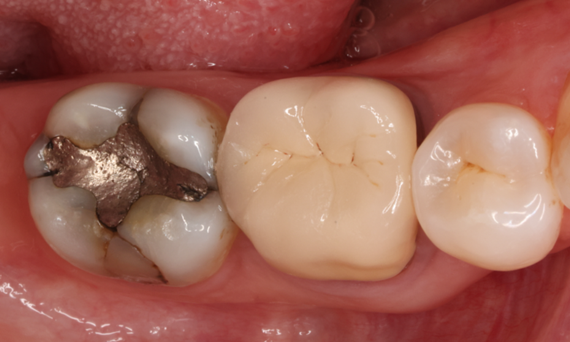

Restauration de la deuxième molaire mandibulaire en consultation

Couronne partielle CEREC Tessera

Une deuxième molaire mandibulaire sensible présentait des fissures ainsi qu’une restauration composite de classe I étendue sur la face vestibulaire. Conformément au concept mini-invasif, une couronne partielle CFAO a été planifiée, fabriquée et collée à l’aide du CEREC Tessera en une seule visite.

Avant : Restauration en amalgame défaillante nécessitant un remplacement. Patient se plaignant de sensibilité et dent présentant de multiples fissures.

Après : Restauration d’une couronne partielle CFAO réalisée en consultation avec la vitrocéramique CEREC Tessera Advanced Lithium-Disilicate.

Carlos Eduardo Sabrosa

Rio de Janeiro, Brésil